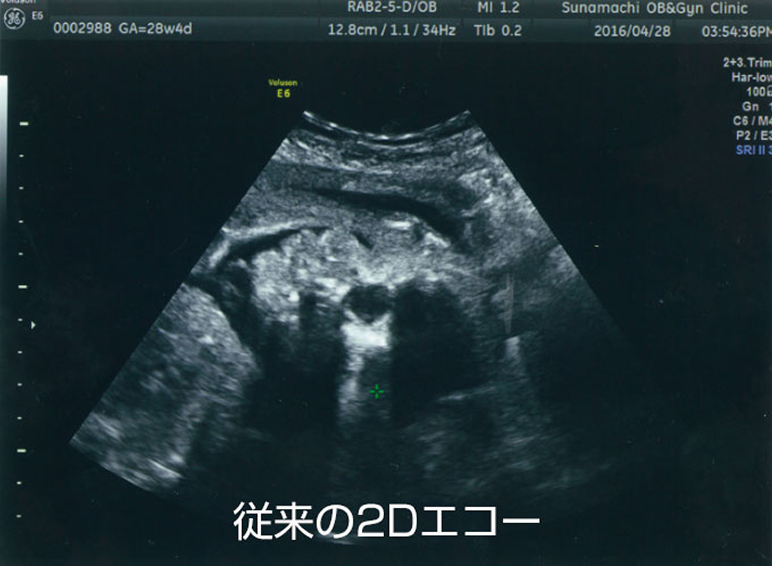

プレミアム4D エコー</span > Premium 4D Echo

4Dエコーについて

おなかの中で、すくすく育つ赤ちゃん。そのかわいいしぐさや表情を見てみませんか?

4D(3D)エコーとはお母さんのお腹に超音波をあて、赤ちゃんを立体的に映す技術です。 お腹の赤ちゃんとビデオ通話をしているような、今だけの思い出を作ってみませんか? タイミングがよれば大きなあくびや、指しゃぶりの瞬間が見られることも!

当院のプレミアム4Dエコーはエコー検査のスペシャリスト、専門資格を持った女性超音波検査士が担当します。 さらに超音波診断装置には、美しい画像に定評のあるGEヘルスケア社プレミアム超音波診断装置・Volusonシリーズ(HDlive機能搭載)を使用しています。

超音波検査士よりポイント

- おすすめは妊娠28週~30週ごろ。赤ちゃんの姿や表情が特にキレイに写ります。

- 当院の4Dエコーの特徴は最先端のHDlive機能!とても鮮明で分かりやすい

動画でご覧いただけます。 - 羊水量により映像が不鮮明になったり、

赤ちゃんの姿勢や向きで表情が見られないこともあります。